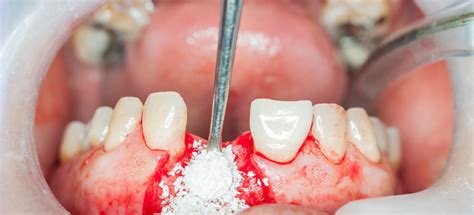

El procedimiento generalmente sigue estos pasos:

- Preparación del sitio receptor: limpieza y preparación del área donde se colocará el injerto.

- Selección y preparación del material de injerto: dependiendo de las necesidades específicas del paciente.

- Procedimiento quirúrgico: se realiza una incisión en las encías, se coloca el injerto y se cierra la zona tratada.